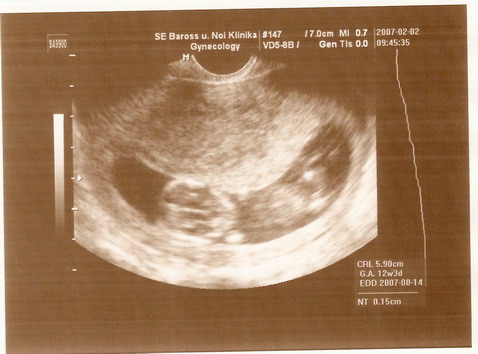

Képzeljétek, betöltöttem a 12. hetet, bár kevesebb kiló vagyok, mint terhesség előtt és elég sokat hányok is, de azért elég jól érzem magam. Holnap délelőtt megyek a doktor bácsihoz és este megírom nektek a híreket.

Szóval, pénteken voltam a doktorbácsinál és ultrahangon.

Íme az eredmény:

Kép 12. heti UH

5,9 cm-esek vagyunk. Na mit szóltok?

A doktorbácsi is elégedett, mert mindent rendben talált.

Remélem így is marad!